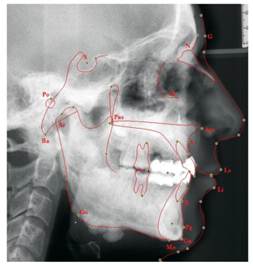

Figure 6

Tracing lateral cephalometric radiograph of the patient. Ricketts' analysis is illustrated. G = glabella; N = the anterior point of the intersection between the nasal and the frontal bones; Or = the lowest point of the inferior margin of the orbi; Pn = pronasale; Po = the midpoint of the upper contour of the external auditory canal; Pns = posterior nasal spine; Ans = anterior nasal spine; A = the innermost point on the contour of the premaxilla between anterior nasal spine and the incisor tooth; Pg = the most anterior point on the contour of the chin; Gn = the most anterior and inferior point on the mandibular symphysis; Me = the most inferior point on the mandibular symphsis; Go = the midpoint of the contour connecting the ramus and body of the mandible; Ba = the lowest point on the anterior margin of the foramen magnum, at the base of the clivus; Ar = the point of the intersection between the shadow of the zygomatic arch and posterior border of the mandibular ramus.

Dental volumetric tomographic (DVT) images showed multiple osteomas of the buccal cortex of the right mandibular angle and left mandibular angle (Figure 3,4). Additionally, in the coronal and sagittal sections of the mandible condyle, a huge osteoma that limited mouth opening was diagnosed (Figure 5). Cephalometrically, he showed a slightly retrusive maxilla with an ANB angle of 1˚and a relatively normal mandibula in anterioposterior direction. His mandibular plane angle (S-N / Go-Me: 25˚) and articular angle (S-Ar-Go: 133˚) were reduced (Table 1). His profile was straight due to the slightly retruded maxilla position. According to the Steiner's S line his lips were in normal position (Figure 6). The osteomas were submitted for pathologic examination. Histopathologic examination revealed that the specimens displayed a normal-appearing dense compact lamellar bone with minimal marrow spaces and rare irregular Haversian canals that did not show osteoclasts or osteoblasts (H&E X100)(Figure 7). Due to the dental anomalies, the osteomas in the mandible and the familial history of the patient, the patient was diagnosed as GS. Following resection of the osteomas that caused discomfort, prosthetic rehabilitation was performed.

Table 1

Measurement of the internal cranial structures

Skeletal MeasurementsNormal ValuePatient's Value

SNA8280

SNB7979

ANB31

A - B(OP)-10

Npog-FH (Facial plane)8589

S-Ar-Go143133

Ar-Go-Gn130126

S-N/Go-Me3225

S-N-Gn(Y axis)6768